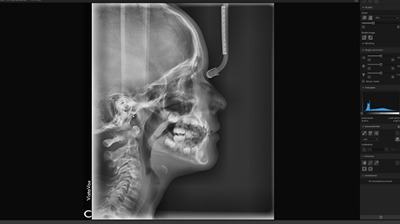

With the aid of innovative and extensive tools using artificial intelligence, cephalometric analyses can be completed within a few seconds using VistaSoft Trace. This user-friendly software add-on identifies reference points and soft tissue silhouettes automatically and plots them on the X-ray image.